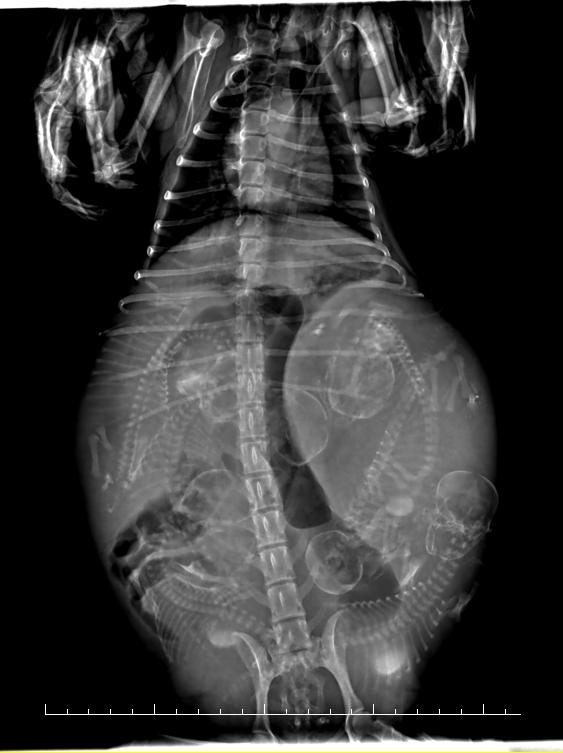

DR显示

6个胎儿胎位不正后脚朝下

编辑

初步诊断

狗狗同时两个胎泡流出,

DR显示有可能两个胎儿堵在阴道上端,

建议家长为狗狗选择剖腹产手术。